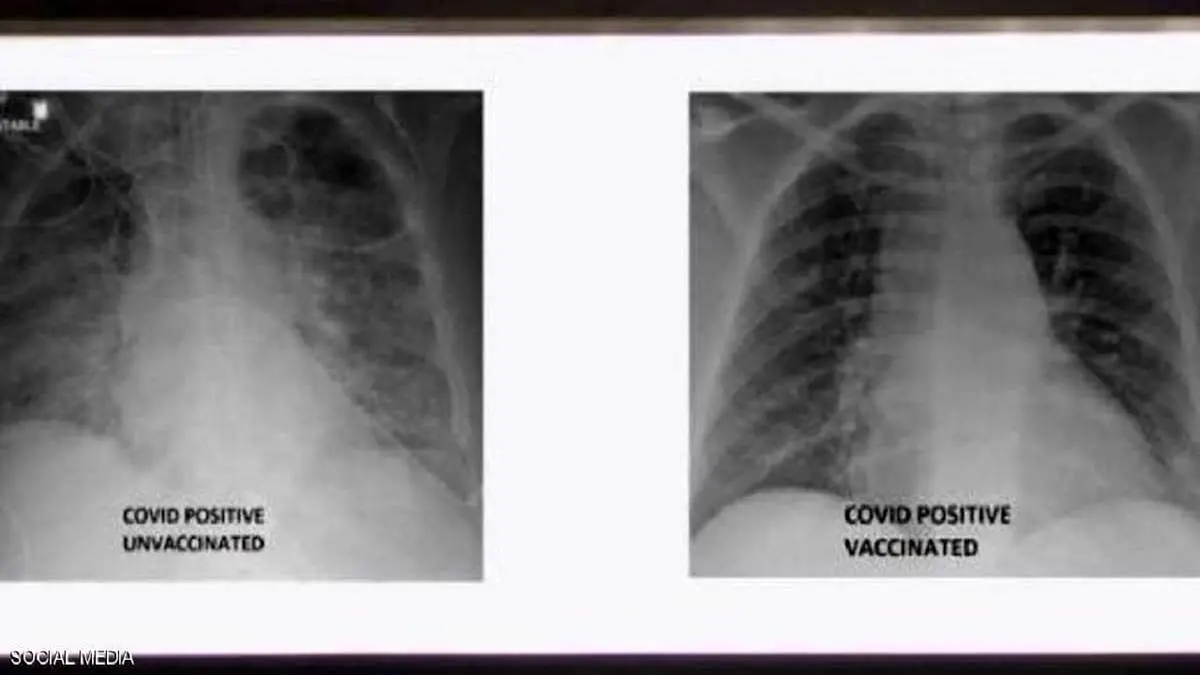

تفاوت ریههای فرد واکسینه شده و فرد واکسینه نشده/ببینید

یک پزشک آمریکایی تصویری را از ریه های فرد واکسینه شده و فرد واکسینه نشده مبتلا به کرونا منتشر کرد.

به گزارش منیبان به نقل از اسکای نیوز، غسان کمال پزشک عرب در ایالات متحده، تصویری را منتشر کرد که تفاوت بین ریههای فردی که در برابر ویروس کرونا واکسینه شده بود، با ریههای شخص دیگری که واکسن دریافت نکرده بود به نمایش گذاشت و نشان میدهد هر دو نفر به ویروس کرونا مبتلا شده اند.

تصاویر اشعه ایکس نشان میدهد که ریههای فرد واکسینه نشده آلوده به ویروس کرونا تقریباً سفید بوده و به عنوان "تیرگی ریه" شناخته میشود، به این معنی که آنها در این ویروس آغشته شده اند، در حالی که تصاویر ریههای فرد دیگر سفیدی کمتری دارد.

تصویر مورد اول همچنین به معنای کمبود هوا در ریههای فرد است، در حالی که در مورد دوم به این معنی است که هوا به راحتی جریان مییابد، علاوه بر این ریههای او عاری از ویروس است.